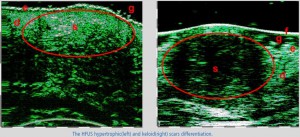

-Διαφοροποίηση μεταξύ υπερτροφικών και χηλοειδών ουλών

-Διάγνωση μορφών ακμής